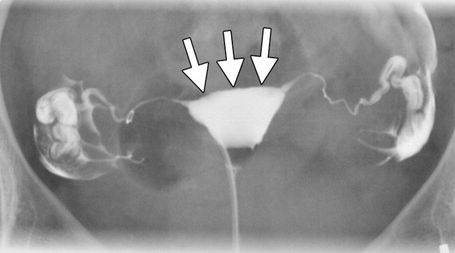

Uterus post-DES

- Risque augmenté de Clear Cell Carcinome Ovarien